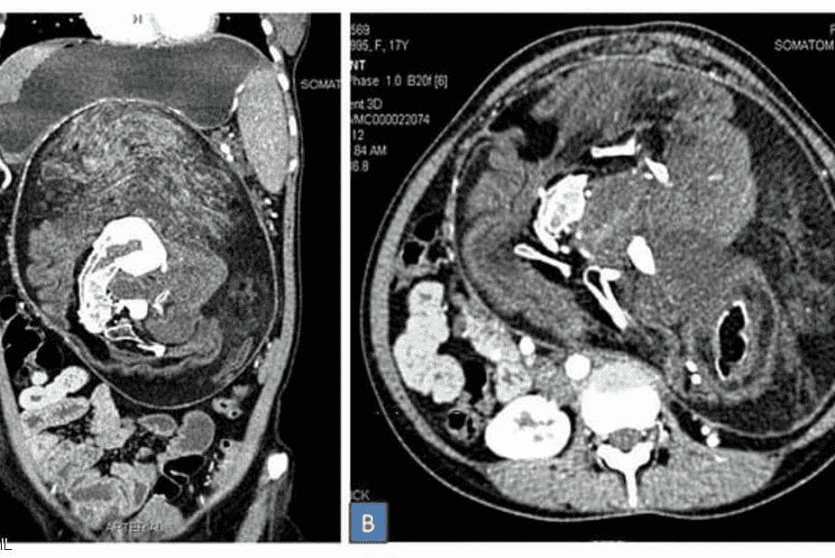

وبعد إجراء تصوير بالأشعة والتصوير المقطعي، اتضحت طبيعة الكتلة الغريبة داخل أحشاء الفتاة وتم التعرف عليها على أنها مجموعة كاملة من الأعضاء والأنسجة، وبدت بعض المناطق مثل الدهون، بينما ظهرت مناطق أخرى مثل الأنسجة الرخوة للأعضاء، ثم بعض الأجزاء الصلبة المكونة من الكالسيوم، والتي بدت بيضاء صارخة في التصوير بواسطة الأشعة المقطعية.

وعند الفحص الدقيق، تبين أن أجزاء الكالسيوم ما هي إلا عظام، وعلى وجه التحديد، فقرات وأضلاع وعظام طويلة.

كان ذلك قبل عامين، عندما قرر الأطباء إجراء عملية جراحية لإزالة هذه الكتلة، التي تبين أنها تحتوي بالفعل على العظام والشعر وعدة أسنان بالإضافة إلى "هياكل تشبه براعم الأطراف".